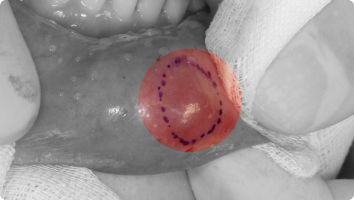

점액낭종은 입술이나 뺨 안쪽에 생기는 투명하거나 푸른빛의 물집 같은 혹입니다.

침샘이 다쳐서 침이 고이면서 발생하는 경우가 많습니다.

보통 통증은 없지만, 자꾸 커지거나 재발할 수 있습니다.

- 국소마취 후, 혹과 주변 침샘을 함께 절제하여 제거합니다.

- 크지 않고 안전한 수술로, 대부분 당일 바로 일상생활이 가능합니다.

- 재발 방지를 위해 병소를 확실하게 제거하는 것이 중요합니다.

하마종은 혀 밑에 생기는 큰 물집 같은 혹으로, 점액낭종이 큰 침샘(혀밑샘)과 연결되어 발생하는 경우가 많습니다.

커지면 말하거나 음식을 먹을 때 불편할 수 있습니다.

- 국소마취 후, 혹을 완전히 절제하기보다 조대술(구멍을 만들어 침이 빠지도록 하는 방법)을 시행합니다.

- 병소의 벽을 일부 열어주어 침이 고이지 않고 자연스럽게 배출되게 합니다.

- 수술 시간이 짧고, 회복도 빠른 편입니다.